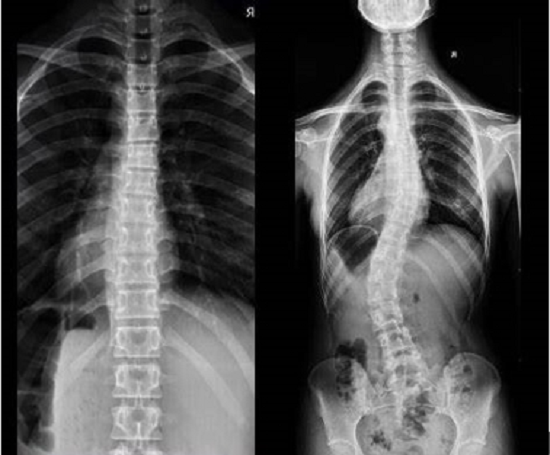

案例展示

脊柱侧弯的孩子坚持训练后也会有明显的收获